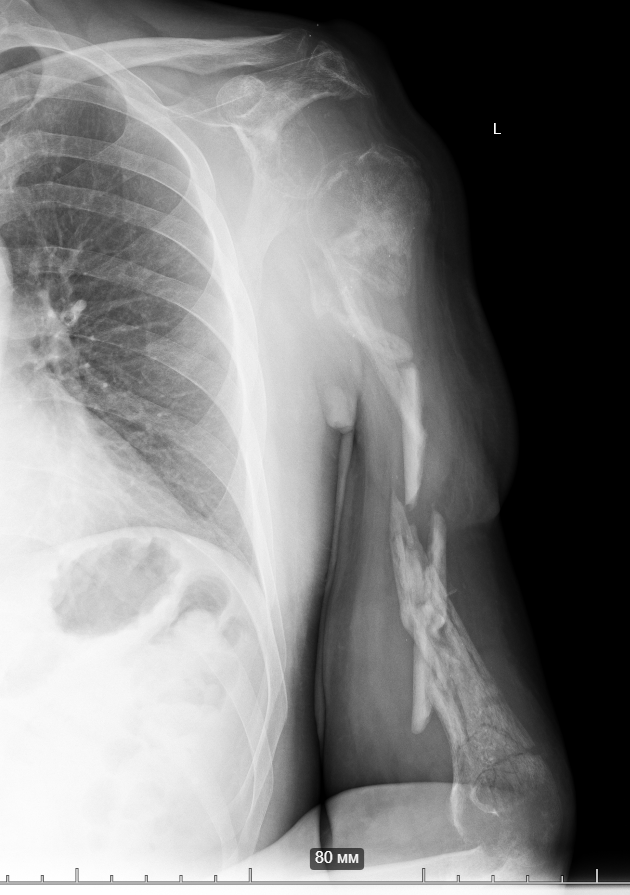

A soldier (now demobilized) sustained a blast injury in February of this year.

Six procedures were initially performed to begin the limb-salvage process for the arm (external fixation and wound debridement).

Despite the wound becoming infected with a “military” bacterium (American surgeons refer to this and Acinetobacter as the “Iraq bacteria” or “veterans’ disease”), Ukrainian doctors were able to manage the infection.

Simultaneously, several skin grafting procedures were carried out. One of Ukraine’s best plastic surgeons performed a thoracodorsal flap. The wounds have healed. The patient was transferred to us after 6 weeks of rehabilitation.

But the “Iraq bacterium” (named after the experience of wounded U.S. veterans) proved to be a particularly insidious microorganism.

So, together with Vasyl Parii and Denys Dolgush, instead of performing massive bone grafting immediately, we decided to stabilize the severely damaged humerus (see X-rays) with a plate using a minimally invasive approach — and took new tissue samples for culture. In peacetime and in case of a normal civilian injury (usually the main bacteria in such cases is Staphylococcus Aureus), we would do bone grafting simultaneously with internal fixation. But the presence of the “Iraqi bacteria” in early investigations does not allow this; the risk of severe complications is too high.